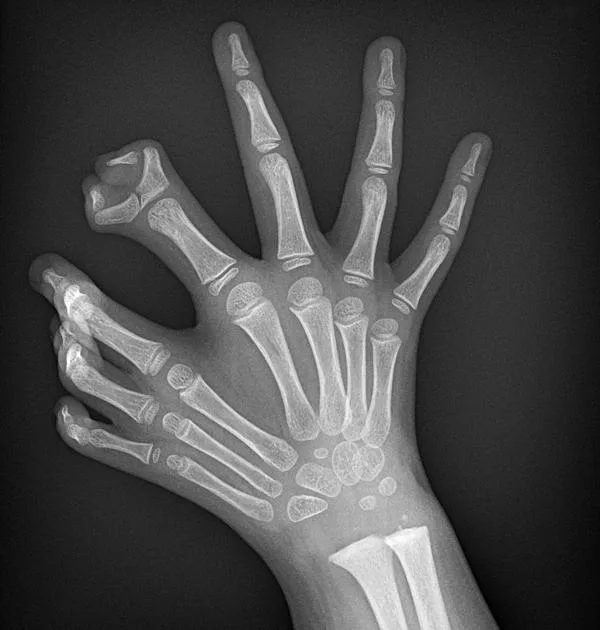

The images reveal one of the rarest congenital anomalies in medical history: ulnar dimelia, commonly known as mirror hand. This condition transforms a human hand into a perfectly symmetrical, seven- or eight-fingered structure with no thumb, where the ulna (forearm bone) is duplicated, the radius is absent, and the wrist contains twice the normal number of carpal bones. Metacarpals and phalanges are mirrored along a central axis, creating a hand that looks as if it has been reflected in a mirror. Most astonishingly, the tendons are cross-connected: when one finger flexes, its mirror opposite moves in perfect synchronization, producing an eerie, symmetrical motion.

The hand typically features:

- 7–8 fingers (polydactyly) of roughly equal length.

- No thumb—all digits resemble ring or middle fingers.

- Duplicated ulna, absent radius.

- Mirrored tendon arrangement, causing symmetric movement.

Ulnar dimelia is extraordinarily uncommon—fewer than 100 cases have ever been documented worldwide, with many historical reports from the 19th and early 20th centuries. The genetic cause remains elusive, though mutations affecting the sonic hedgehog (SHH) signaling pathway—critical for limb patterning—are strongly implicated. Normally, SHH creates asymmetry (thumb on one side, pinky on the other); when disrupted bilaterally, the limb develops as two ulnar halves fused at the midline.